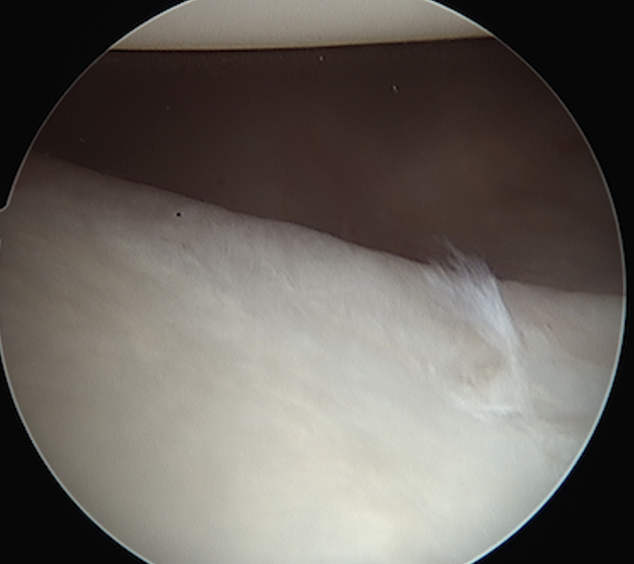

Side to side repair of capsular tear

Intact anterior labrum with capsular tear, axillary nerve seen below capsular tear in axillary recess